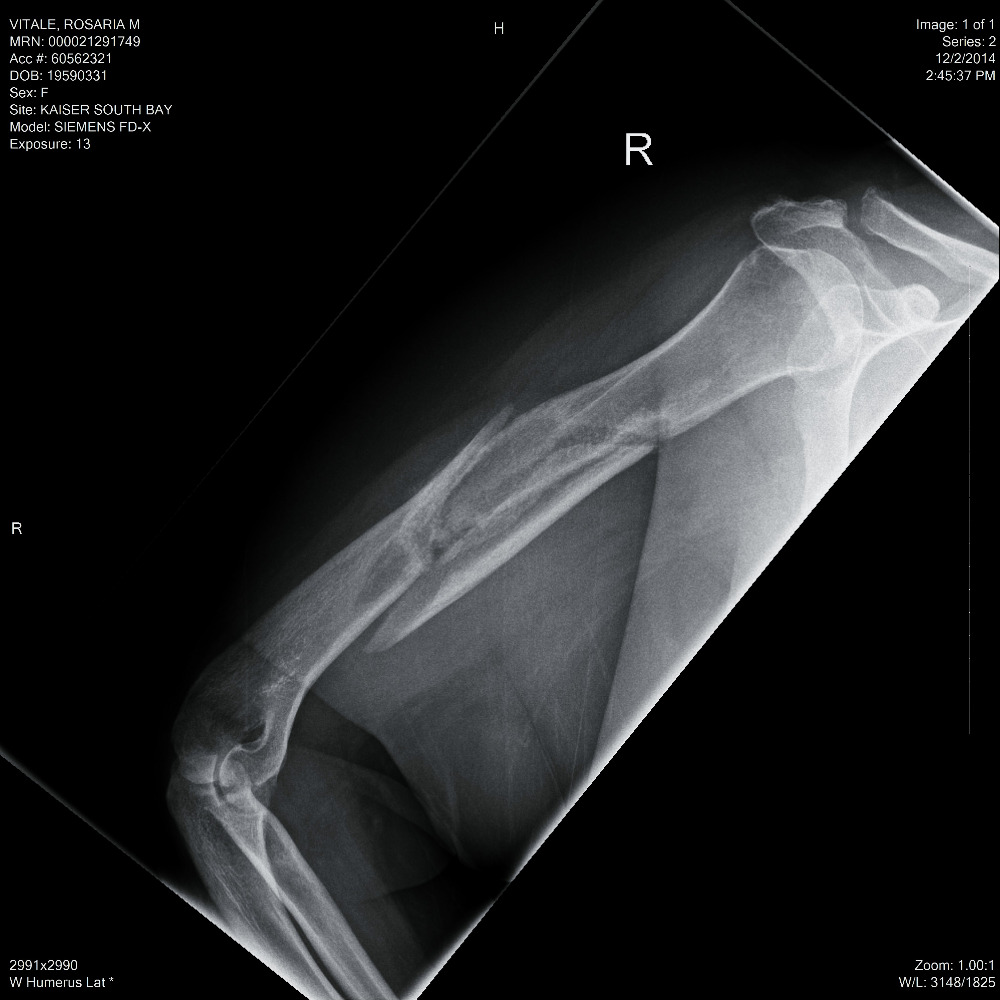

I had my surgery on September 13th, 2016. According to the doctor, it was" very, VERY BAD!" He had to find the nerve buried within the fracture. Carefully move it out of the way before he could clean up the debris of the broken bones. The bicep muscle was caught between the fractures. He had to recut the bone to straighten it out, place a twelve inch long, metal plate with a dozen screws, to hold it all in place. The over two year wait didnt do me any favors. I now have a long healing process and eventually physical therapy. Meanwhile, I no longer have living benefits and I desperately need your continued help. I need to raise a minimum of $4,000 to survive through January 2017. Anything will help, I would be very grateful. Thank you.

I found a good worker comp lawyer and a real ortho specialist. On March 31st, 2015 ( my 56th birthday) I saw the doctor. The X-ray was taken. He took one look and said I needed surgery. It would never heal on its own. He classified it as a "disastrous break." In May, I had an appointment with another specialist. He only worked on upper extremities. Yup, needs surgery, with a rod and some screws and other things. My surgery was set in September of 2015. I would never have 100% use of my right arm, ever again. He didn't know how much damage the break caused, until he cut my arm open. Then a nurse took my blood pressure. It was sky high, 198/110. The doctor nealy fell over and wondered how I was still standing. Now, I needed BP meds and other tests. The insurance company denied 99% of every request. I failed the pre-op and the surgery was cancelled.